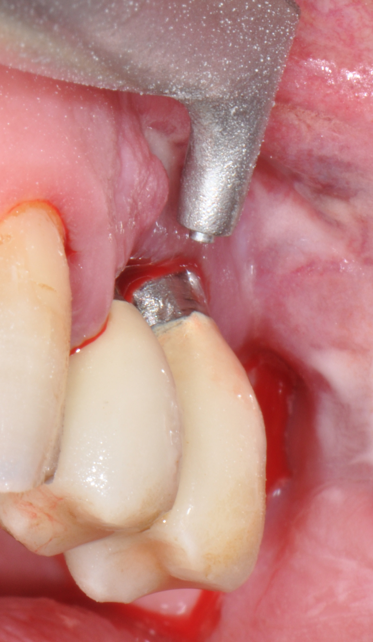

The parameters used to define peri-implant disease usually are: Probing Depth (PD), Crestal Bone Loss (CBL), Bleeding on Probing (BOP) and presence of suppuration and/or fistula.9 Peri-implant mucositis is characterised by soft tissues inflammation witnessed by BOP with or without PD deepening but no effects on the crestal bone while peri-implantitis is characterised by CBL, BOP alone or in conjunction with pus, with or without PD deepening. (Figs. 1, 2 and 3) display the diagnostic steps of a case of peri-implantitis. While mucositis allows a complete healing, peri-implantitis is not reversible.12

Fig.1: Case 1. Peri-implant probing reveals a PPD of 9mm and pus.

Fig.2: Case 1. BOP starts immediately after probing.